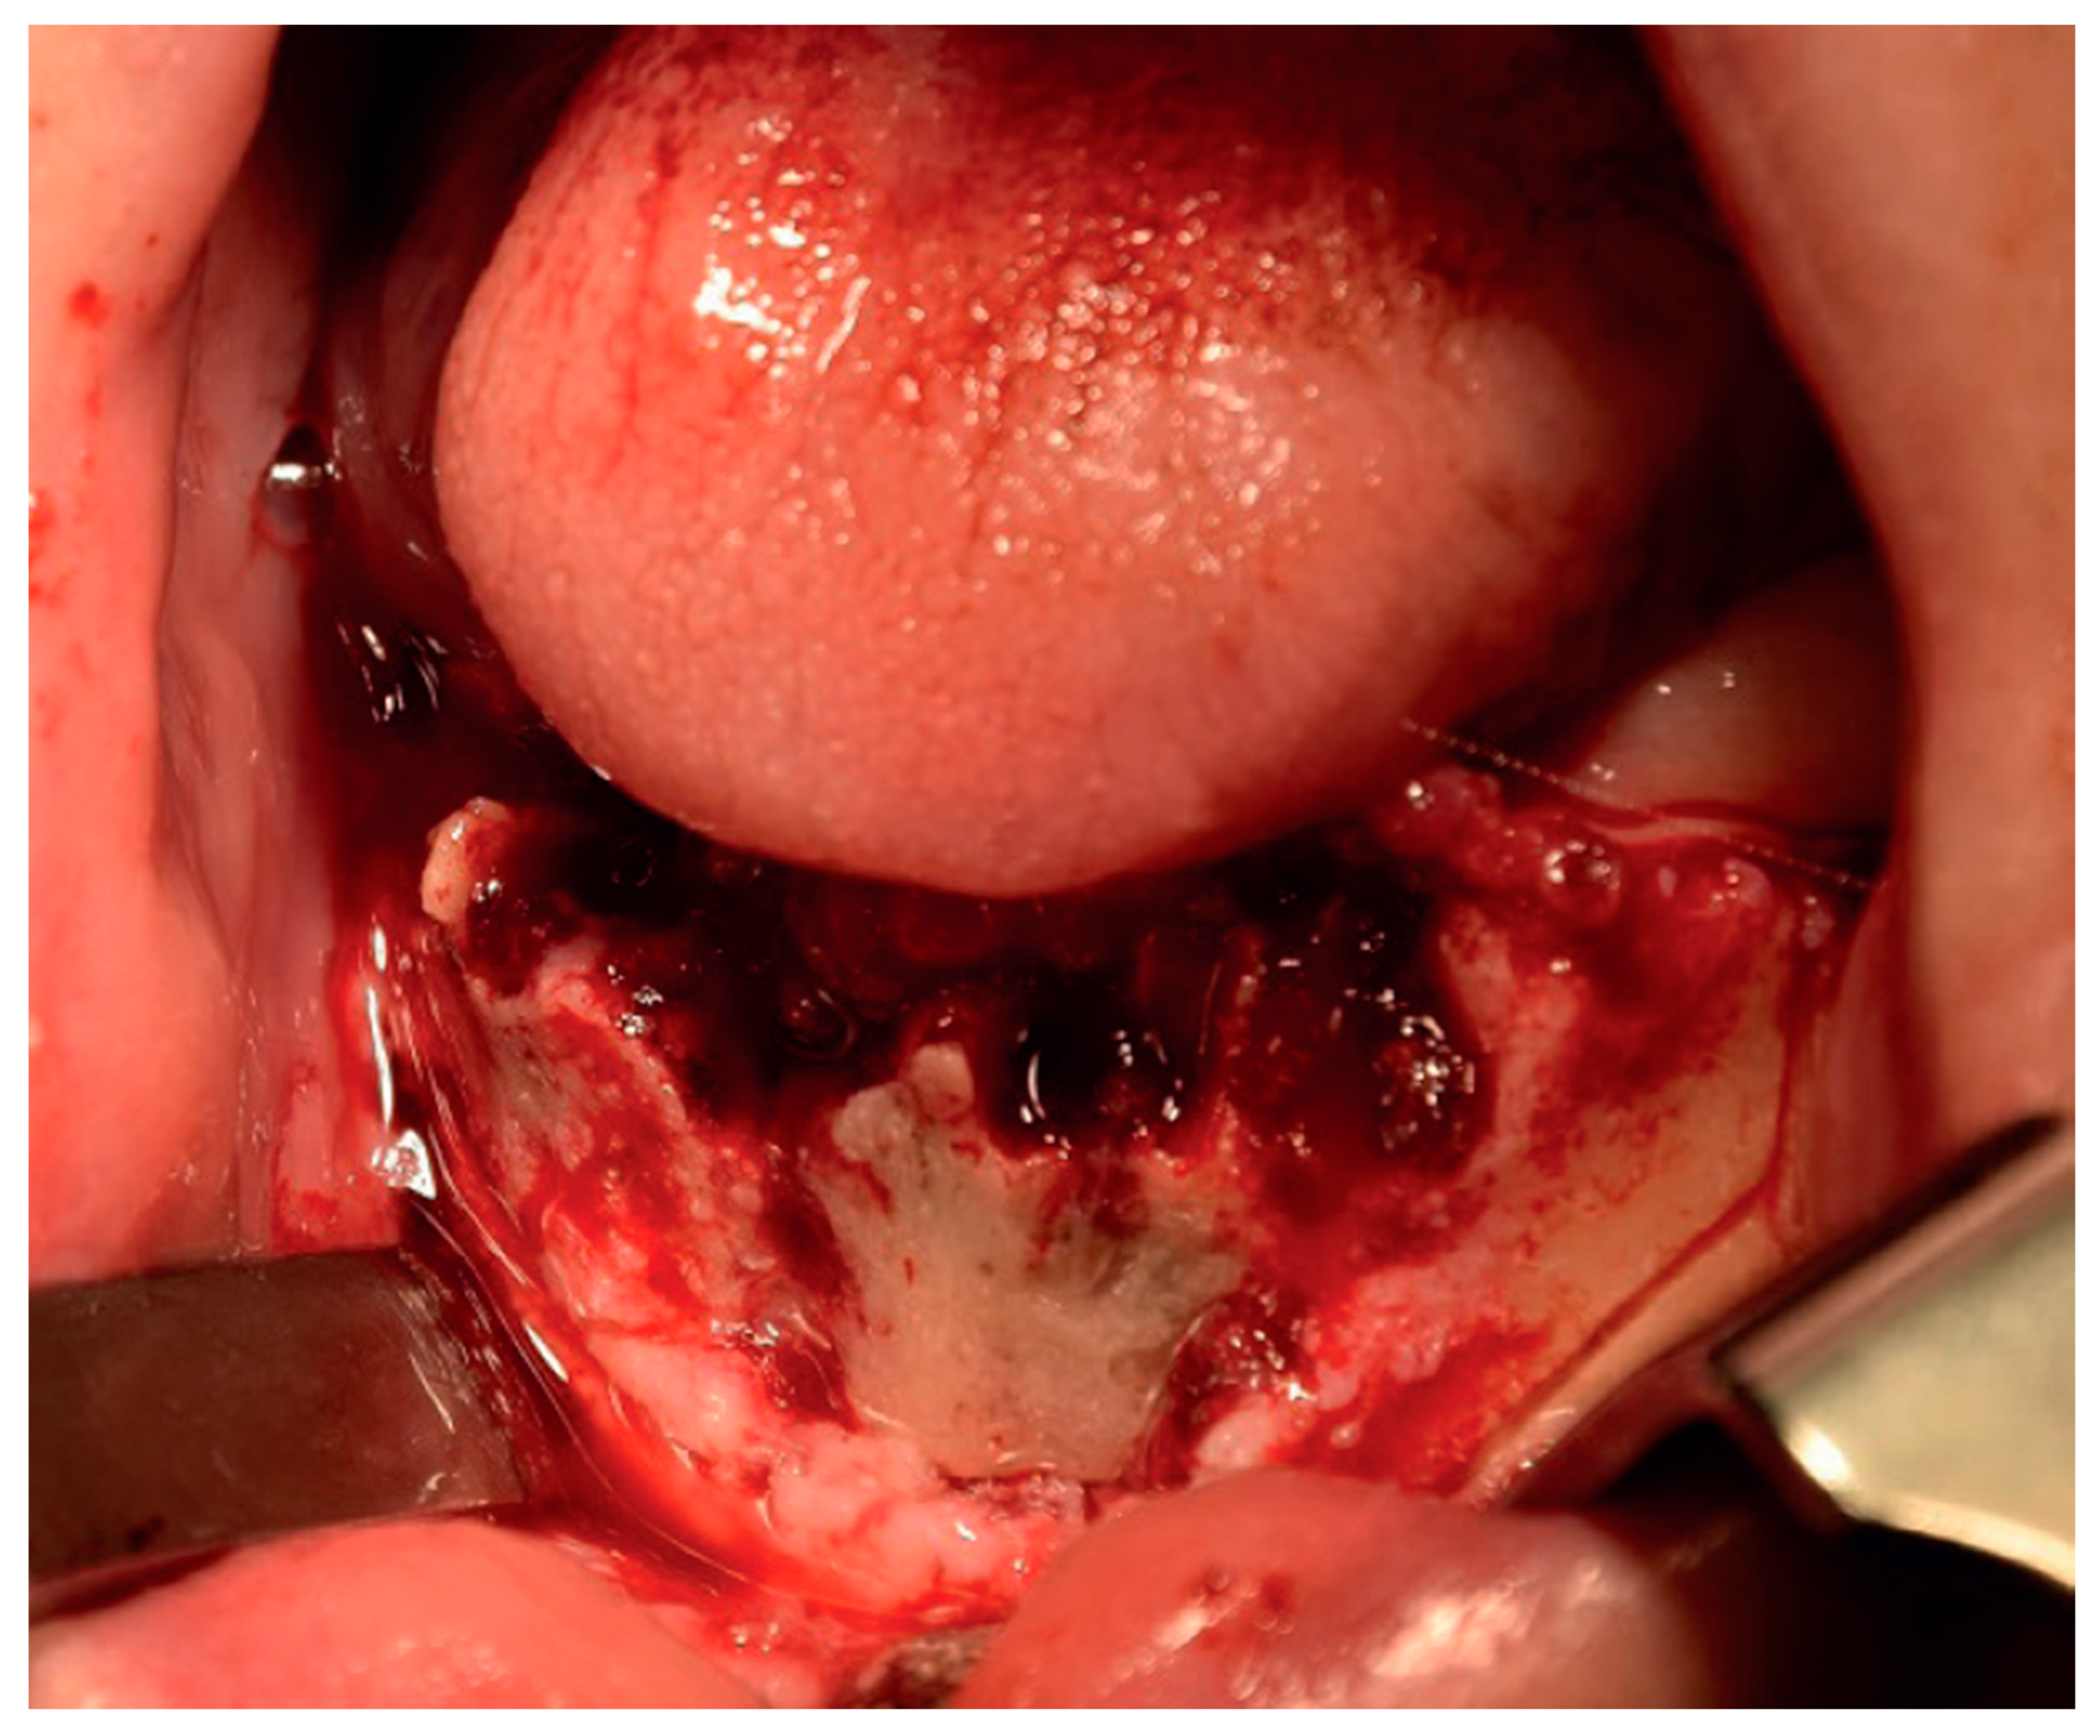

2.5. Therapeutic Intervention